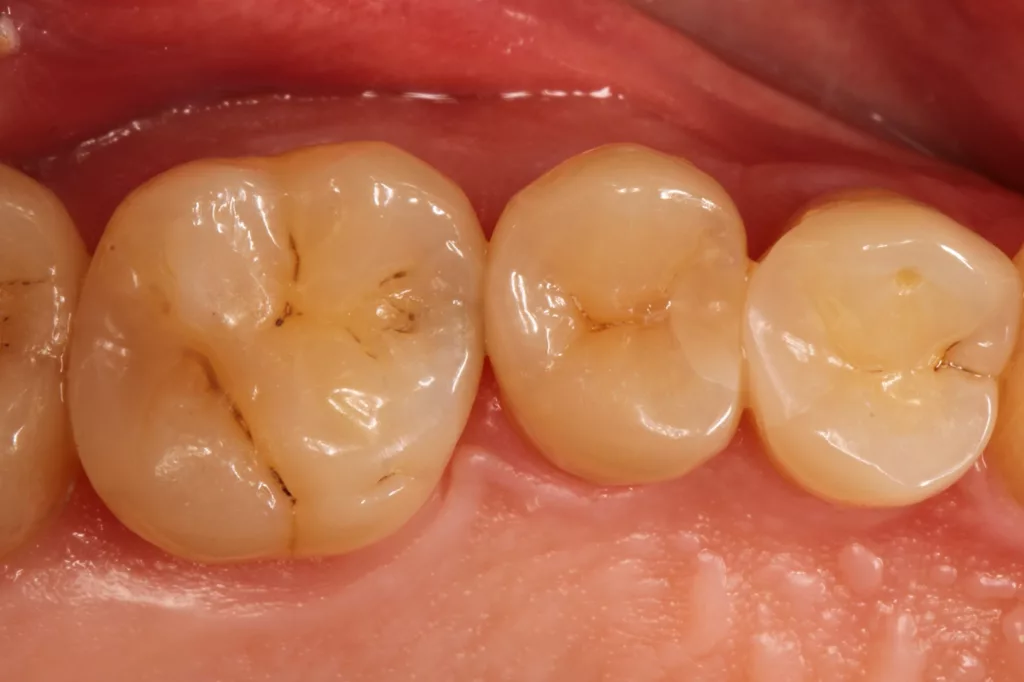

Das Restaurationsprozedere folgte den vorangegangenen Fällen. Die Polymerisation von Adhäsiv (G2 Universal) und des Bulkflow-Komposites (Visalys Bulk Flow) erfolgte hingegen separat und nicht mit einer gemeinsamen Abdeckung beider Kavitäten mit dem 10 mm Lichtleiter der Elipar Deep Cure, um den Schattenwurf der beiden Teilmatrizen zu minimieren. Die Nachpolymerisation nach Abnahme beider Matrizen erfolgte hingegen nur einmal für beide Kavitäten: einmal von okklusal zentral und mittig auf beide, gerade neu aufgebaute Randleisten und einmal von approximal/bukkal. Das klinische Endergebnis überzeugte erneut funktional und ästhetisch. Die Abbildung 23 zeigt die klinische Kontrolle nach sechs Monaten: Es sind weder Randverfärbungen noch Desintegration erkennbar, die Ästhetik ist ebenso unverändert.